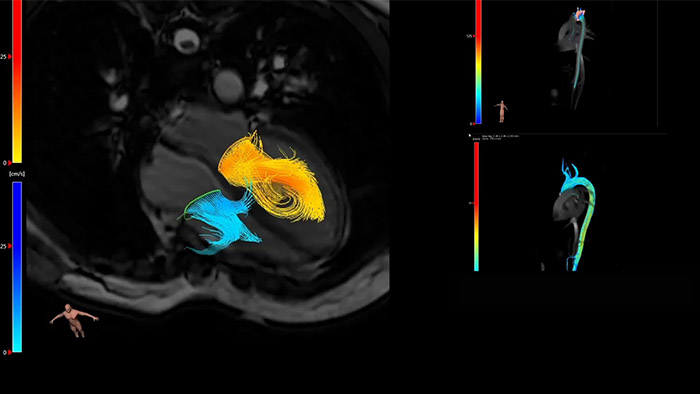

IntelliSpace Portal MR Caas5,6 4D Flow è una soluzione di post-elaborazione che consente di generare ricostruzioni volumetriche 3D per visualizzare e valutare il flusso di sangue in strutture cardiovascolari come le valvole cardiache, le camere e i vasi in base alle immagini MR 4D Flow.